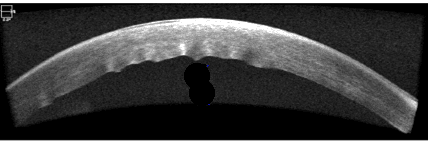

She presented with complaints of blurry vision for two weeks. Her corrected visual acuities were 20/125 OD and OS without improvement by pinhole OU. Pupils were equal, round and reactive to light without a relative afferent pupillary defect OU. Visual fields were full to confrontation OU. Extraocular muscles were unrestricted and had a full range of motion in all gazes. The cornea of the right eye had central microcystic edema and a 1 mm paracentral area of bullae with grade 3+ stromal edema with endothelial folds. The cornea of the left eye had central microcystic edema with grade 2+ stromal edema with endothelial folds (Figures 1-3). Corneal pachymetry revealed central corneal thicknesses of 764 um OD and 771 um OS. The iris was unremarkable in each eye and the anterior chambers were deep and quiet. The crystalline lenses were clear both centrally and peripherally. The IOP was OD 13 mmHg and 11 mmHg. Funduscopic assessment revealed flat optic nerves with distinct disc margins and cup-to-disc ratios of 0.35/0.35 OU with healthy rim and normal macula OU. The peripheral retina was flat and intact OU.